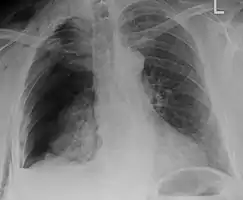

Right sided pneumothorax and rib fractures

Plain X-rays often pick up displaced fractures but often miss undisplaced fractures.[13] CT scanning is generally able to pick up both types of fractures.[13]